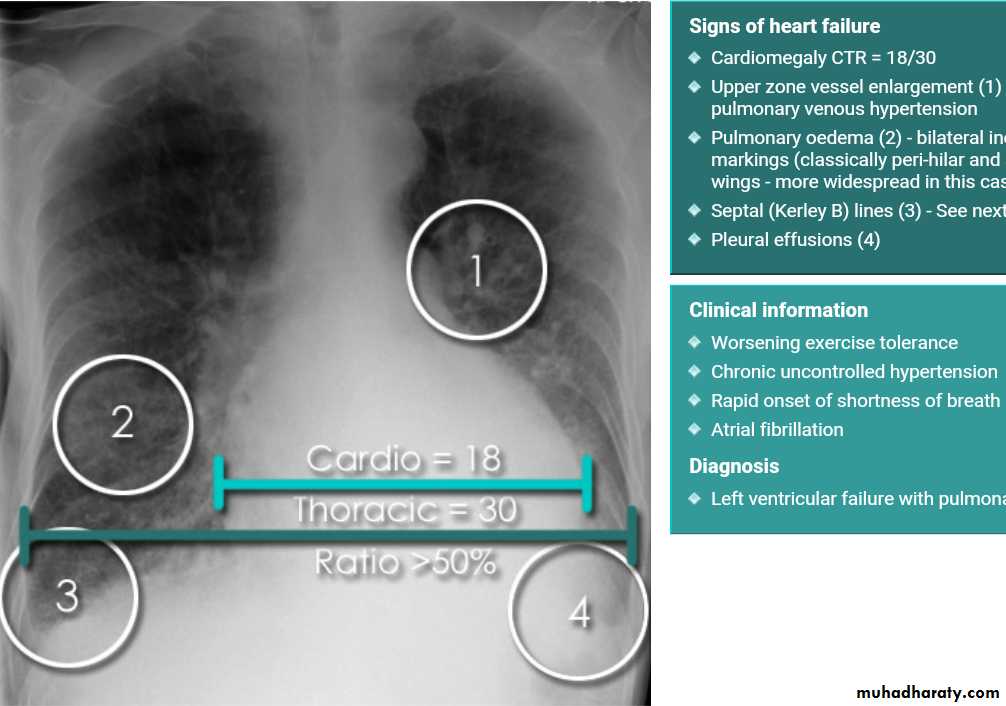

Cardiothoracic ratio (CTR) = Cardiac Width : Thoracic Width

A CTR of greater than 1:2 (50%) is considered abnormal. This however, assumes the projection is Posterior-Anterior (PA), and that cardiac size is not exaggerated by factors such as patient rotation or an incomplete breath in .

The cardiothoracic ratio aids in the detection of cardiomegaly, or more broadly, enlargement of the cardiac silhouette. .

Enlargement of the cardiac silhouette on chest x-ray can be due to a number of causes :

1.cardiomegaly (most common cause by far)2.pericardial effusion

With left sided congestive cardiac failure, the features are that of pulmonary edema which includes:

central pulmonary venous congestion ( prominent hilum )

cephalisation of pulmonary veins ( upper lobe pulmonary venous diversion )

(Septal lines) pulmonary interstitial oedema

pulmonary alveolar oedema

Cardiomegaly

Pleural effusion

radiograph include if pressure > 25 mmHg the findings of :

1.cardiac size/cardio-thoracic ratio: useful for assessing for an underlying cardiogenic cause or association2.Pulmonary Alveolar edema: bat wing pulmonary opacities

3.Pulmonary interstitial edema: presence of peri-bronchial cuffing///septal lines: Kerley lines become more prominent4.pleural effusions

5.Central pulmonary venous engorgement

6.pulmonary blood flow distribution& upper lobe pulmonary venous diversion